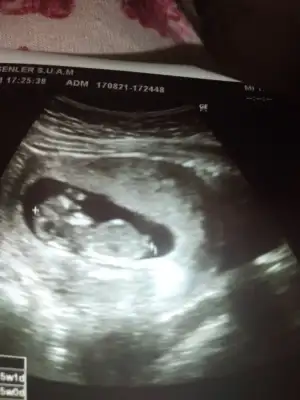

Bir tanesi 12 haftalik ötekilerde 11 haftalk

• 20210817_184335.webp

20210817_184335.webp

23,3 KB · Görüntüleme: 68

• 20210811_171737.webp

20210811_171737.webp

20 KB · Görüntüleme: 80

• 20210811_171659.webp

20210811_171659.webp

22,7 KB · Görüntüleme: 75